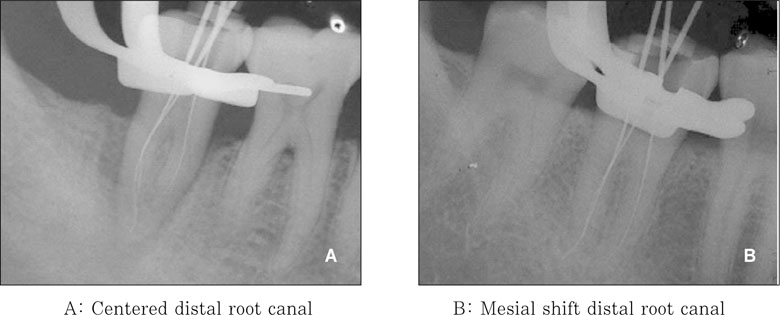

Classification of the location of the distal root canal in a C-shaped root.

jkacd-32-335-g003.jpg

Figure 3 Classification of the location of the distal root canal in a C-shaped root.